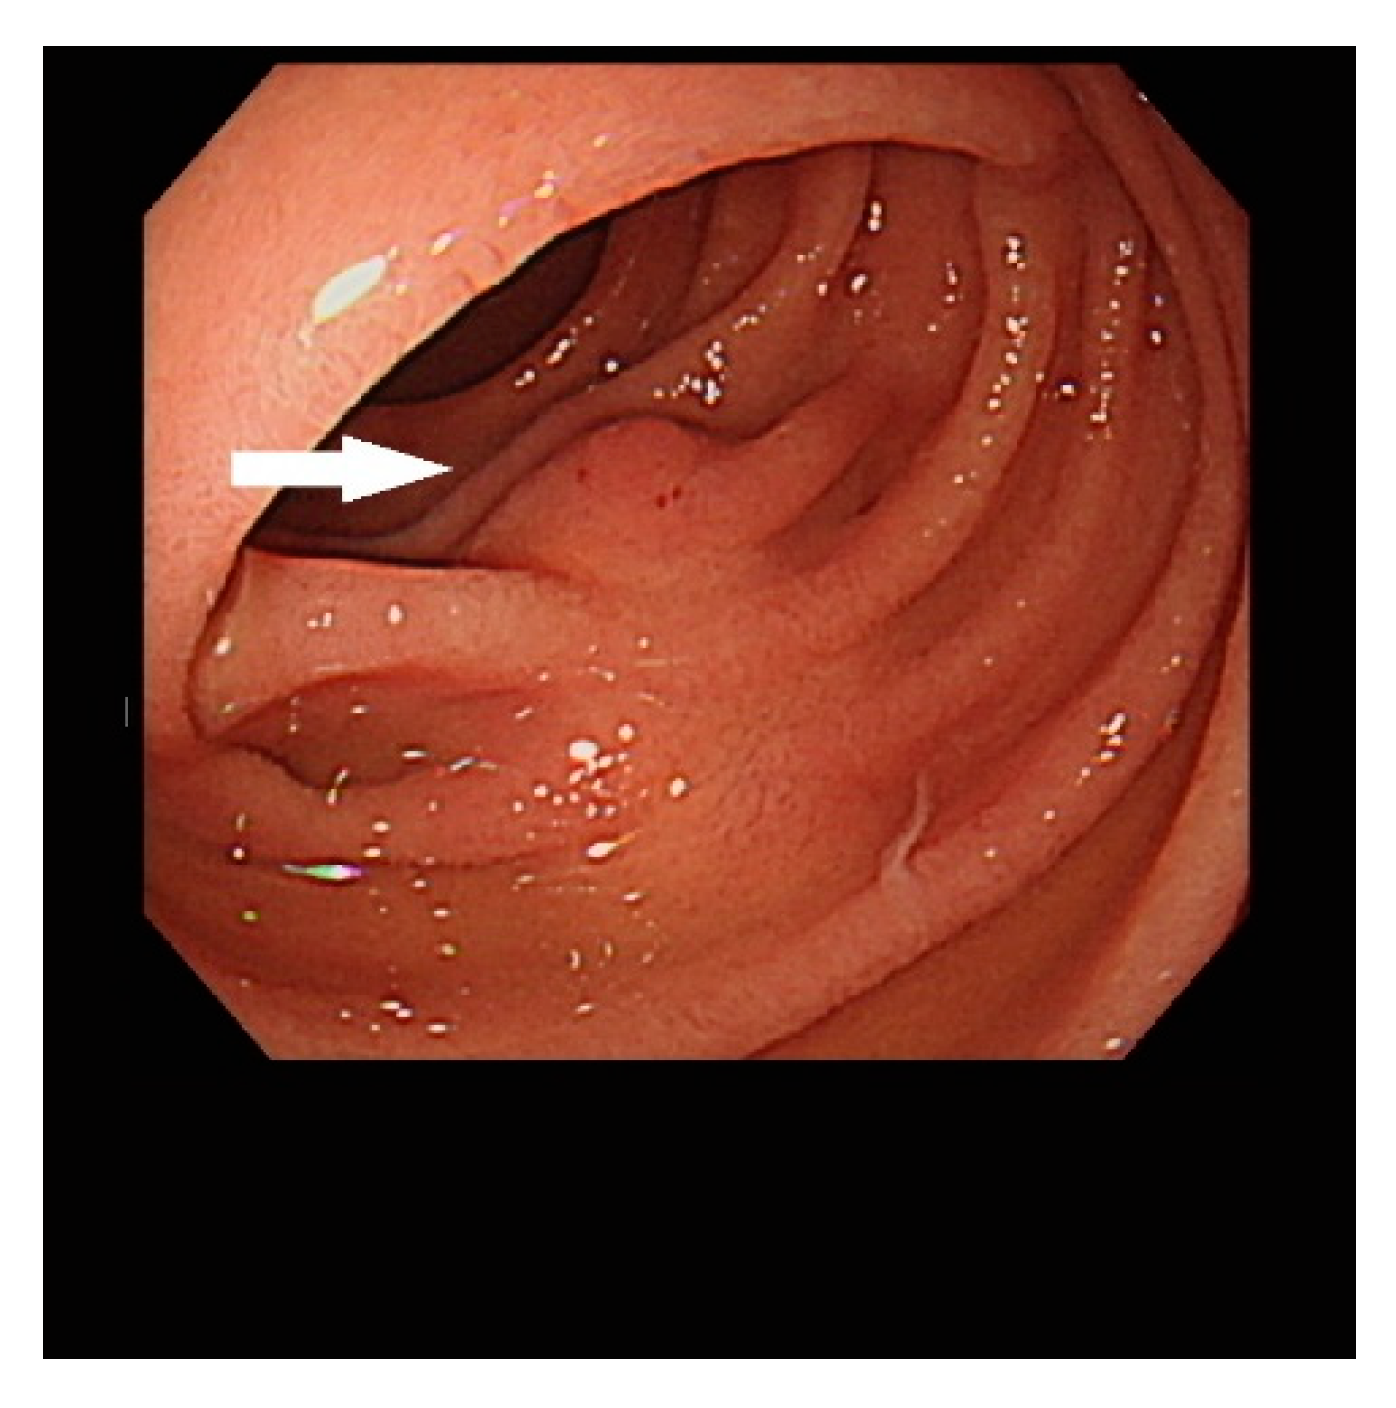

Endoscopic Ultrasound Appearance of Jejunal Ectopic Pancreas Mimicking Metastatic Nodule in a Cancer Patient